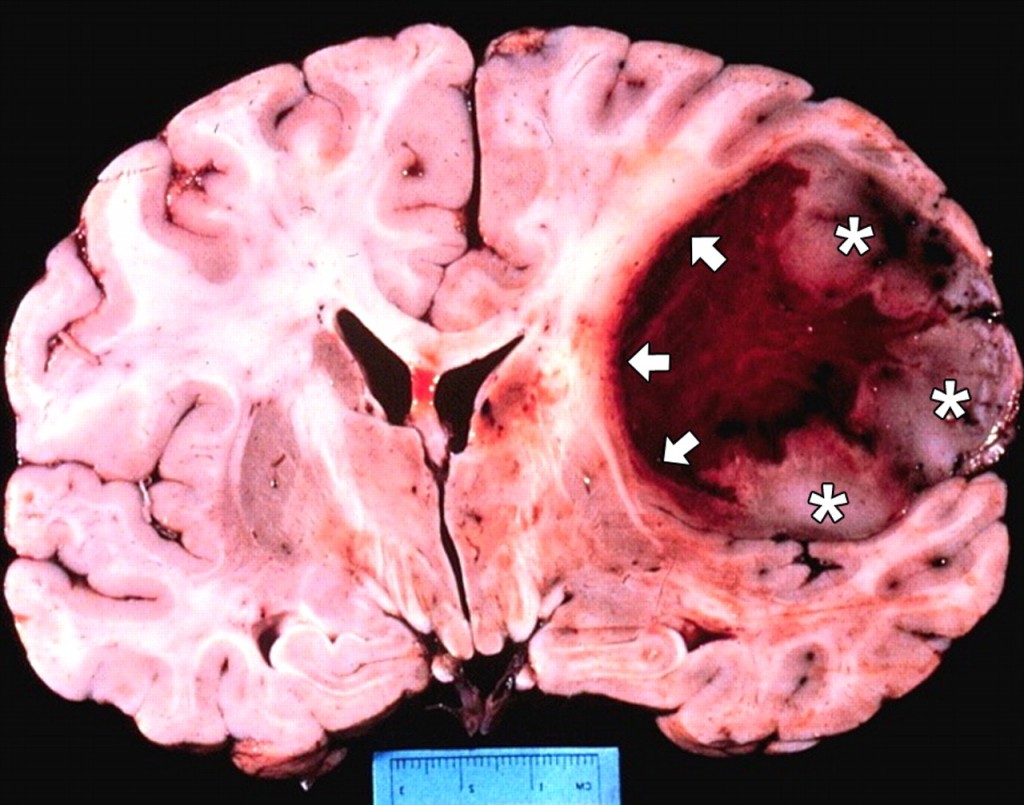

【新聞事件】今天美國(guó)生物技術(shù)公司Celldex腫瘤疫苗Rintega在一個(gè)多型性神經(jīng)膠母細(xì)胞瘤(GBMs)的三期臨床因未能改善總生存期而提前終止。在這個(gè)共有750病人參與、叫做ACT IV的三期試驗(yàn)中,中期分析顯示作為一線用藥Rintega與化療聯(lián)用和單獨(dú)使用化療比未能顯著降低死亡風(fēng)險(xiǎn),中值生存期略短于化療對(duì)照組(20.4對(duì)21.1個(gè)月)。雖然Celldex產(chǎn)品線中還有幾個(gè)其它抗癌藥物,但其股票今天被腰斬。3.9億市值僅比2.9億的現(xiàn)金儲(chǔ)備略高,顯示投資者對(duì)產(chǎn)品線已經(jīng)沒(méi)有太多指望。

【藥源解析】GBMs是最常見(jiàn)的原發(fā)性腦瘤,平均生存期15個(gè)月。Rintega是針對(duì)EGFR一種叫做EGFRvIII突變型的疫苗,由13個(gè)氨基酸接在一個(gè)叫做KLH的載體蛋白組成,已經(jīng)獲得FDA突破性藥物地位。EGFRvIII突變?cè)?4-67%的GBMs有表達(dá)。去年在一個(gè)叫做ReACT的較小二期臨床試驗(yàn)中(73人),作為二線藥物Rintega和羅氏貝伐單抗聯(lián)用和單獨(dú)使用貝伐單抗比顯著改善PFS(11.6對(duì)9.3個(gè)月)。Celldex一度市值達(dá)到20億美元。更有投資者預(yù)測(cè)如果ACT IV成功Rintega可能同時(shí)被批準(zhǔn)用于一線和二線GBMs,Celldex市值可達(dá)8億美元。